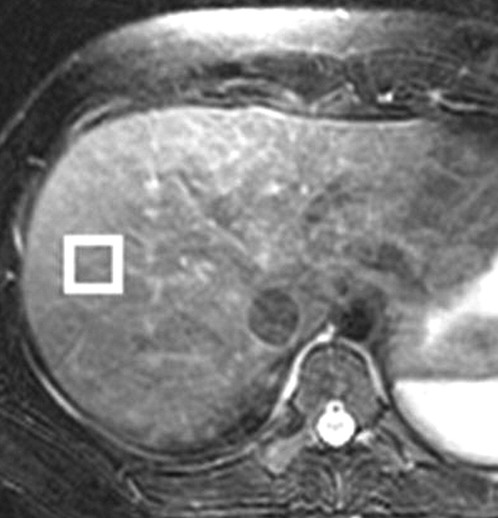

En spectroscopie par RM, les signaux des produits chimiques dans les tissus ou les métabolites sont enregistrés. Les pics de métabolites sont identifiés principalement par leurs fréquences (c'est-à-dire leur position dans le spectre) et sont exprimés comme un changement de fréquence (en parties par million [ppm]) par rapport à une norme. Un spectre de RM donc est un tracé de l'intensité et de la fréquence du signal d'un produit chimique, ou d'un métabolite, dans un voxel donné. Les noyaux les plus couramment utilisés pour la spectroscopie par RM in vivo sont les protons (1H), le sodium (23Na) et le phosphore (31P). Les avantages de la spectroscopie 1H sont qu'elle est plus facile à réaliser, qu'elle est plus largement disponible et qu'elle fournit un rapport signal sur bruit beaucoup plus élevé que le 23Na et le 31P.

Pour la spectroscopie par RM des protons, la fréquence à laquelle un produit chimique ou un composé apparait dépend de la configuration des protons dans la structure de ce produit chimique. Lors de la spectroscopie par RM des protons in vivo, la localisation fréquentielle de l'eau est utilisée comme référence pour identifier un produit chimique. Le décalage de fréquence ou l'emplacement des produits chimiques par rapport à celui de l'eau permet de générer des informations qualitatives et quantitatives sur les produits chimiques présents dans les tissus, formant la base de la caractérisation des tissus par spectroscopie par RM.

La spectroscopie par RM peut également être utilisée pour quantifier la graisse du foie en mesurant les pics lipidiques et pour diagnostiquer la malignité d’une tumeur, généralement en mesurant le pic de choline. L'interprétation des données spectroscopiques par RM nécessite un logiciel de post-

traitement spécialisé et est soumise à des limitations techniques, notamment un faible rapport signal / bruit ou le masquage des pics de métabolites par les pics dominants de l'eau et des lipides. La qualité de cette exploration dépend également de la moyenne du volume partiel à partir d'autres tissus du voxel, ainsi que de la phase et la fréquence passe du mouvement.